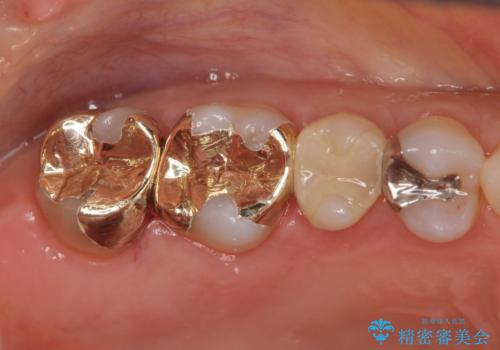

ゴールドは色調がめだつものの上の奥歯はほとんど見えることがないため、色調の問題以上に咬合力が強い場合(ゴールドは破折リスクが低い)や複雑な修復を要する場合(ゴールドは複雑な加工も行いやすく、薄く加工することもできる)に選択をお勧めすることがあります。

今回、噛み合わせが強く、目立たない場所でもあったためゴールドによる修復を行いました。